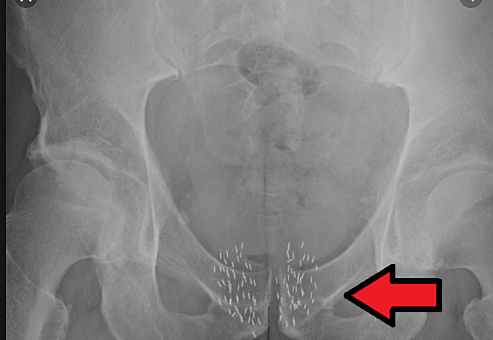

• Implanting Radium

Implanting Radium

Radium tubes were directly implanted into tumors . (Brachytherapy)